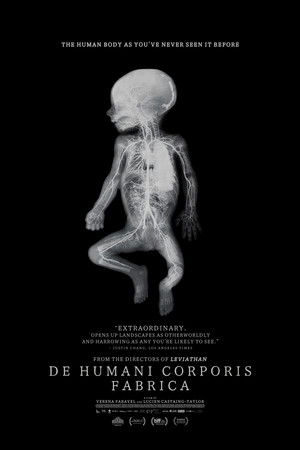

De humani corporis fabrica

(2023)Overview

An extraordinary adventure through the interior of the human body; or the discovery of an alien landscape of unprecedented beauty.